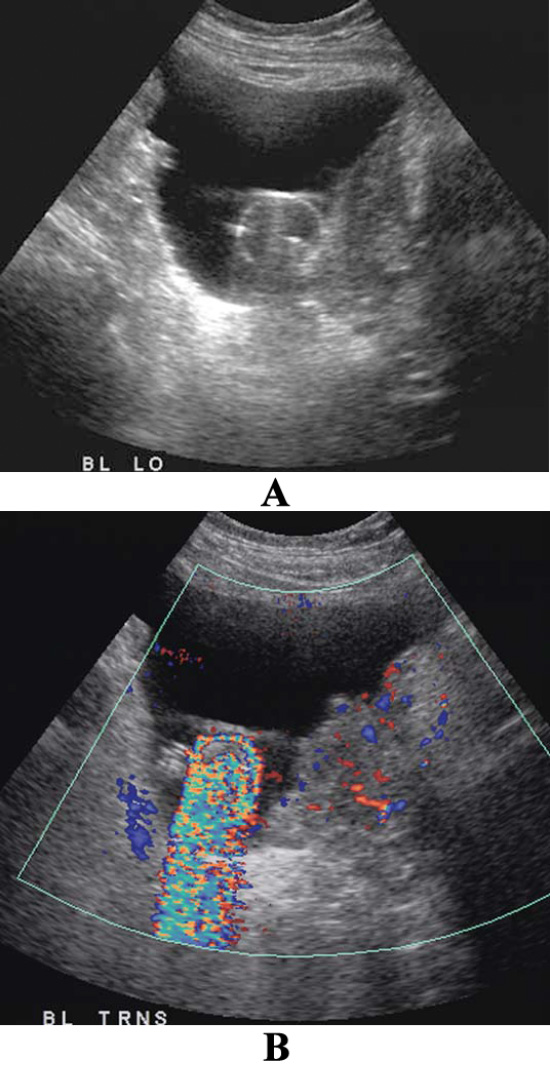

УЗИ брюшной полости: артефакт ложного потока при асците

Фото 5. УЗИ брюшной полости: артефакт ложного потока при асците. А – поперечное изображение в режиме серой шкалы через серповидную связку отмечается анэхогенная жидкость, которая ее окружает. В – цветная допплерография демонстрирует окрашенную жидкость

Артефакт ложного потока позволяет выявить течение жидкости или баллотирование (колебание или смещение анатомического образования в какой-либо полости организма) в местах скопления жидкостей (например, при абсцессе или гематоме, которые могут симулировать объемные образования).